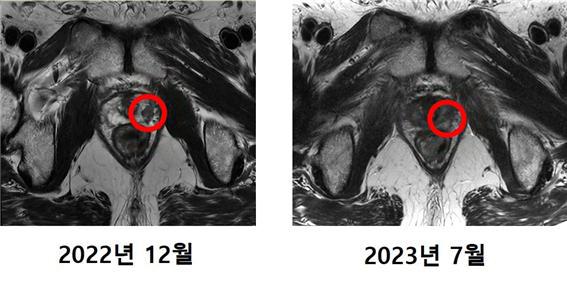

4월 말 치료를 시작한 최씨는 한 주에 3~4회씩 총 12회 치료를 거쳐 5월 중순 모든 치료 과정을 마쳤다. 치료 후 최씨의 PSA 수치는 0.01ng/mL 미만으로 떨어졌고, MRI 촬영 결과 암 조직은 발견되지 않았다.